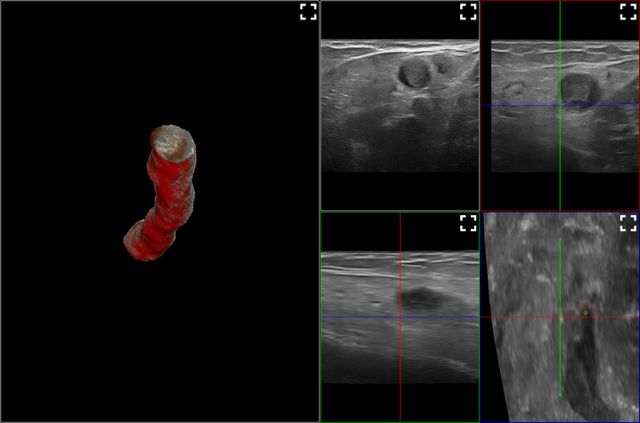

Deuxième cas clinique :

1732213154493

Calcul du taux d’oblitération endovasculaire en 3D, réalisé grâce à l’IA, pour une GVS traitée une semaine auparavant par sclérothérapie échoguidée à la mousse.